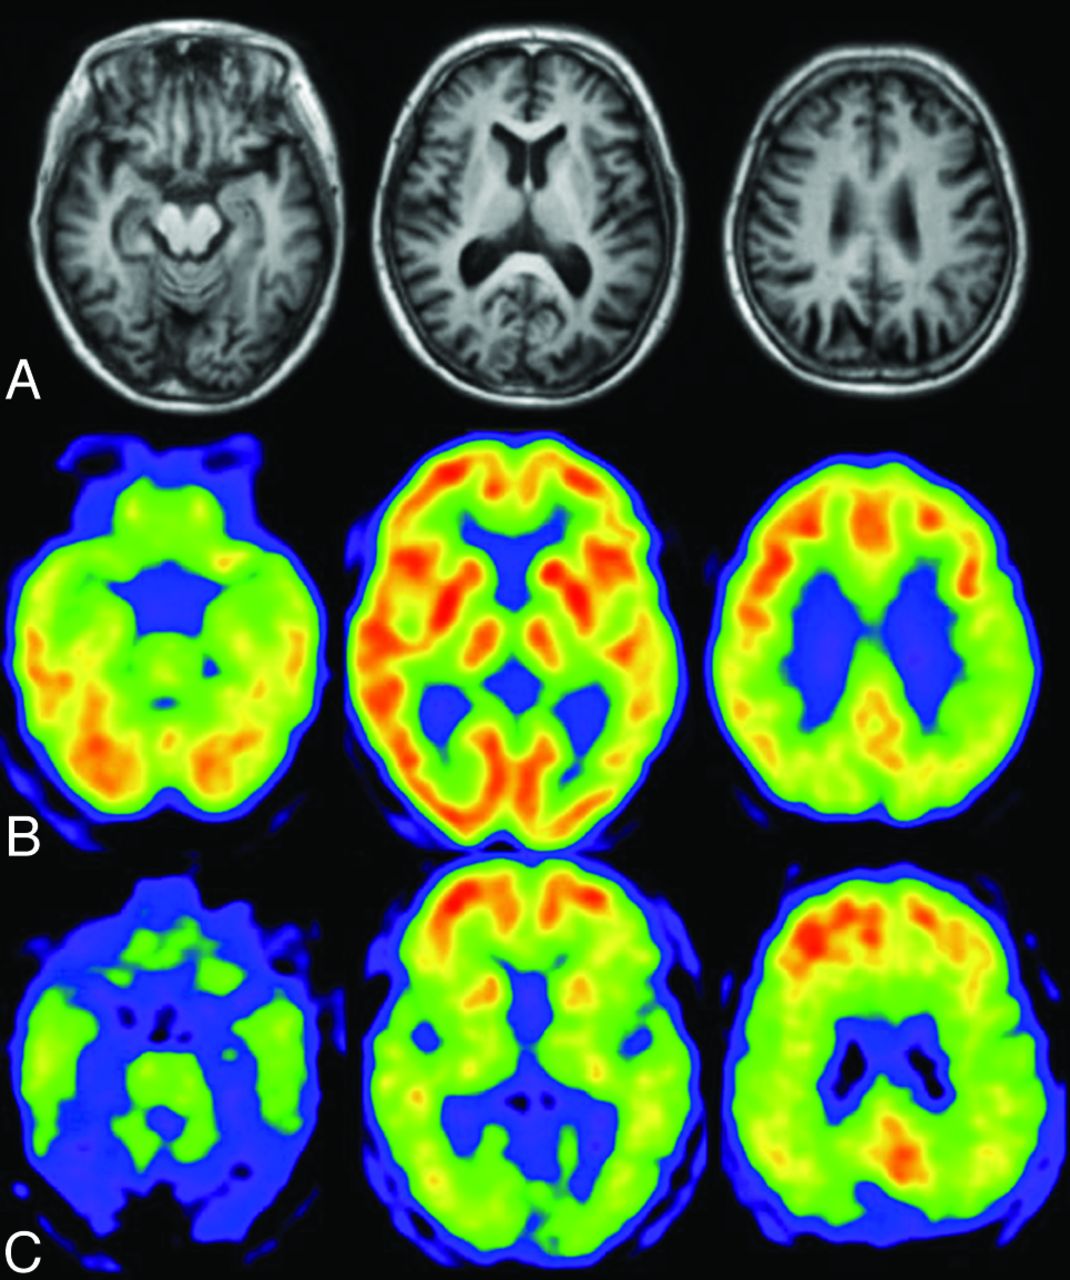

Typical metabolic patterns for different types of dementia compared to …

Dementia, MRI scans – Stock Image – M140/0433 – Science Photo Library

Ct Scan Alzheimer’s Vs Normal – DementiaTalkClub.com

Using MRI scans to reveal early signs of dementia | Health-RI

Frontotemporal dementia, 3D PET scans – Stock Image – C050/0941 …